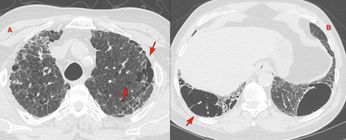

Case 32: Covid-19 - 16.5 Months Follow-Up, Review of Follow-Up Articles and Summary of General Trends Paid Members Public

16 1/2 months follow-up of Covid-19 and other learnings